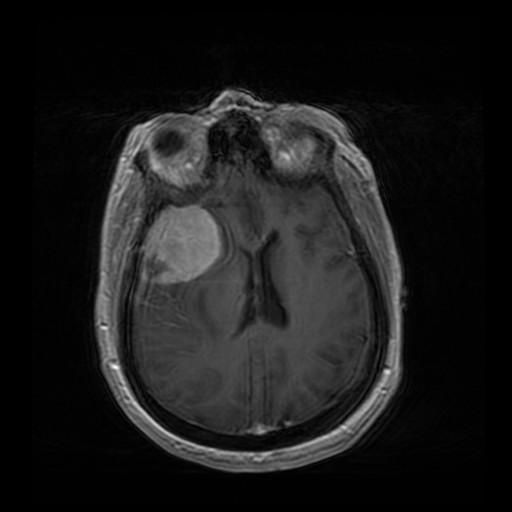

Мононейропатія — це ураження нервового стовбура. Найчастіше її причиною стають травма або тривала компресія нерва. Ураження нерва проявляється порушенням або повною втратою його функції – з’являється слабкість або зниження чутливості в зоні іннервації.

Причинами ушкодження нерва можуть бути:

- хронічні захворювання (пухлини, цукровий діабет, атеросклероз).